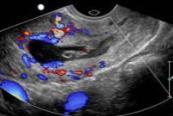

Video 12. Live adnexal ectopic pregnancy - Cervix (Illustration 12)

- Illustration 12. Transvaginal ultrasound showing peritrophoblastic blood flow on color Doppler suggesting implantation of the gestational sac into the cervix.